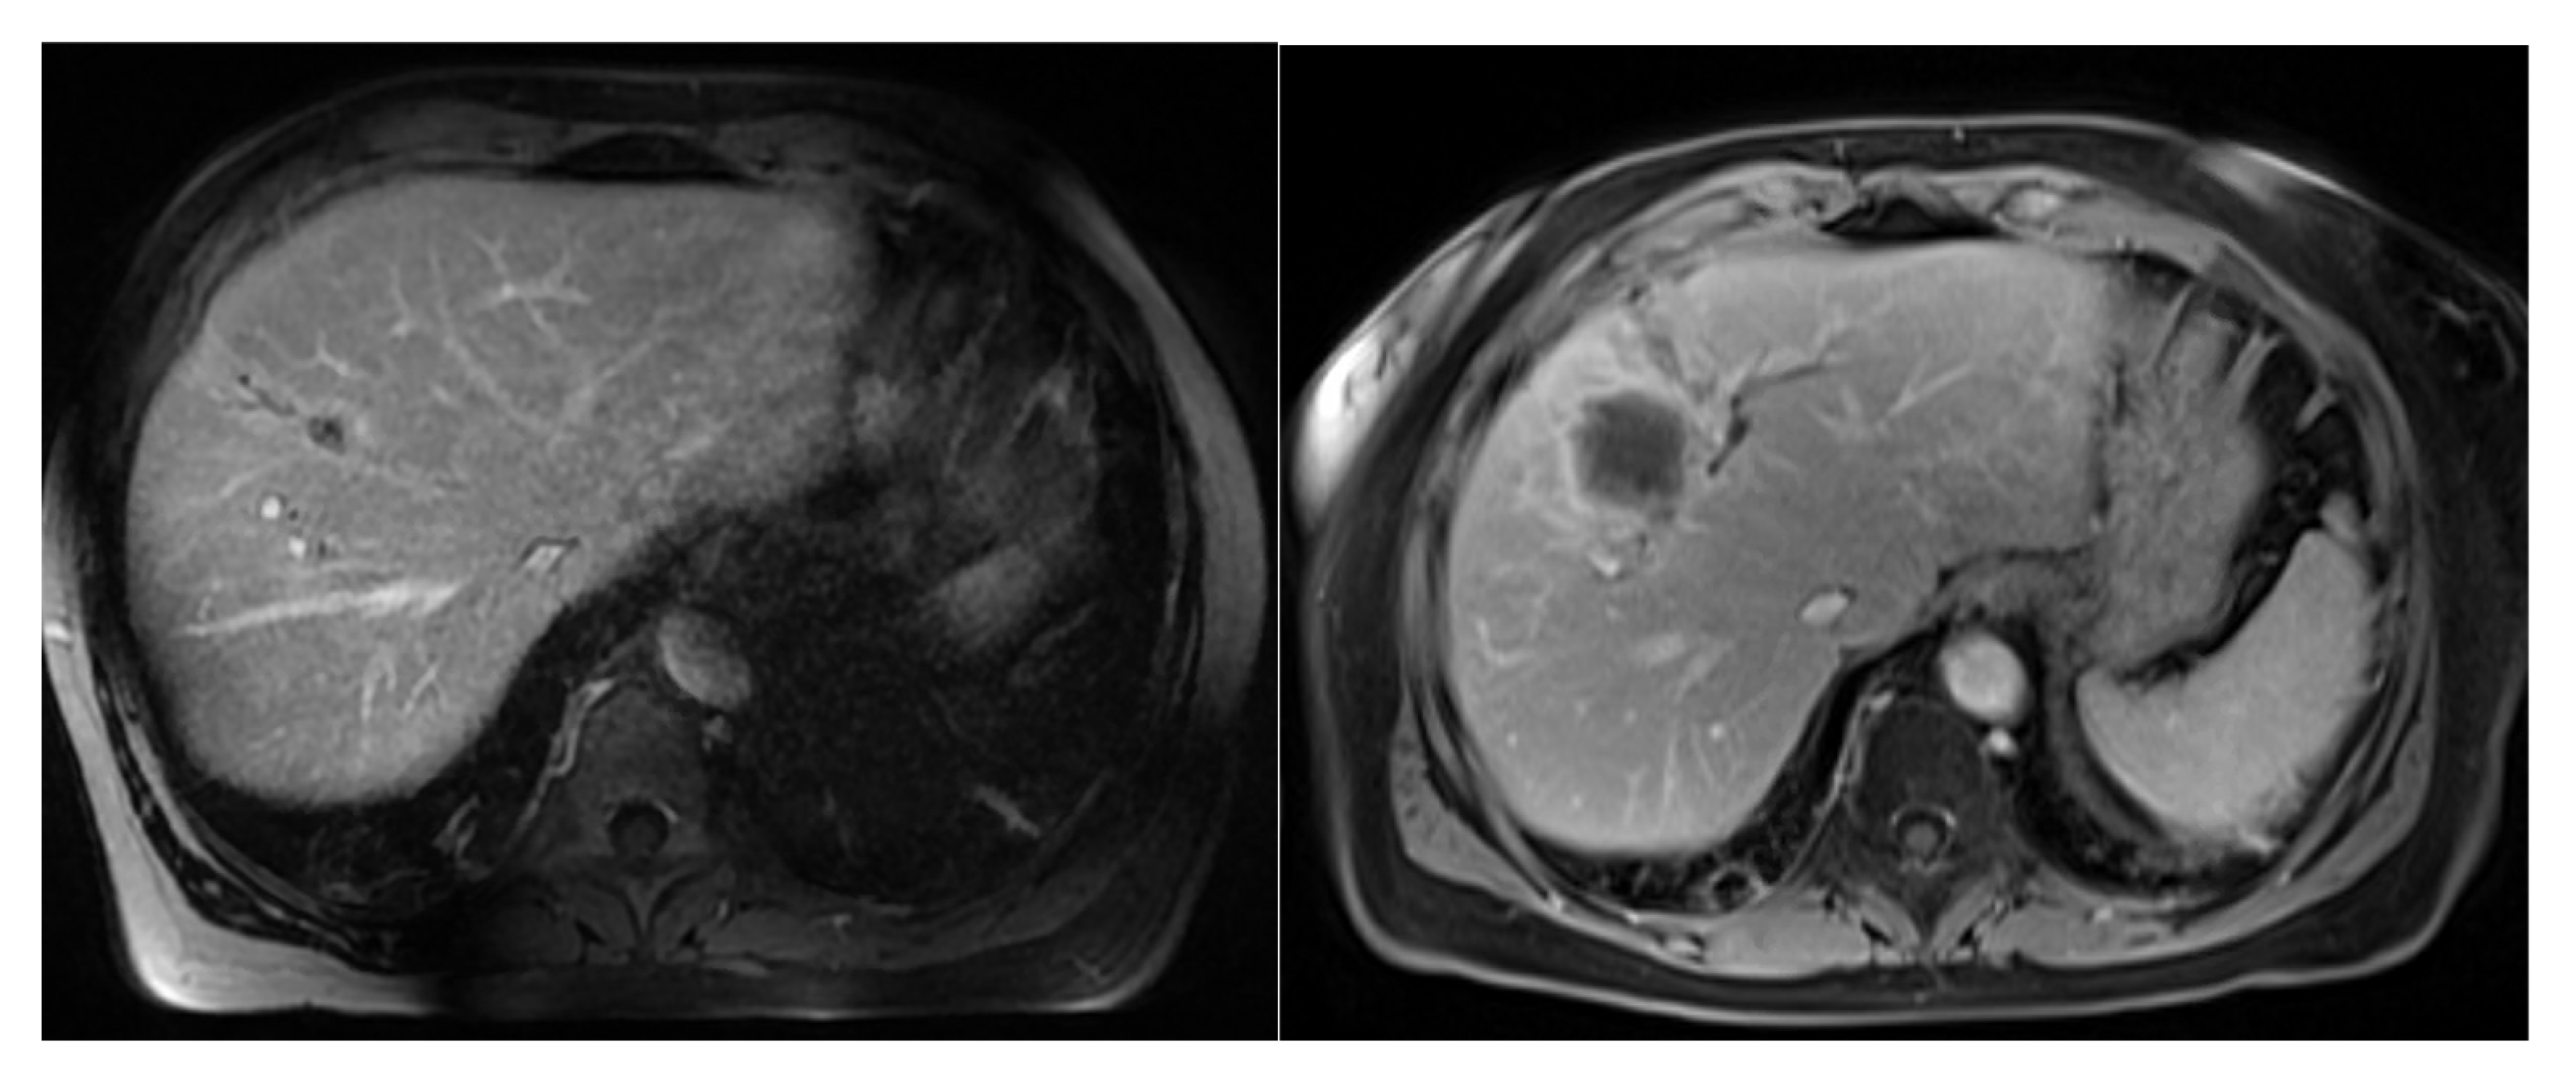

2.2. Radiotherapy Planning and Delivery

2.3. Clinical Assessment, Dosimetric Evaluation and Endpoints